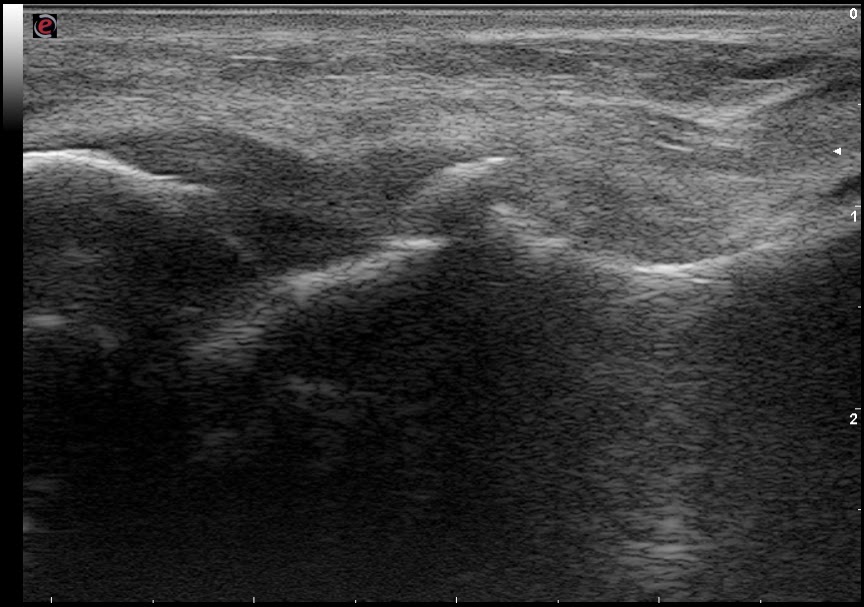

| LTFA: ant. talofibular lig., FL: fluid, AV: avulsion |

- Ligamentous injury